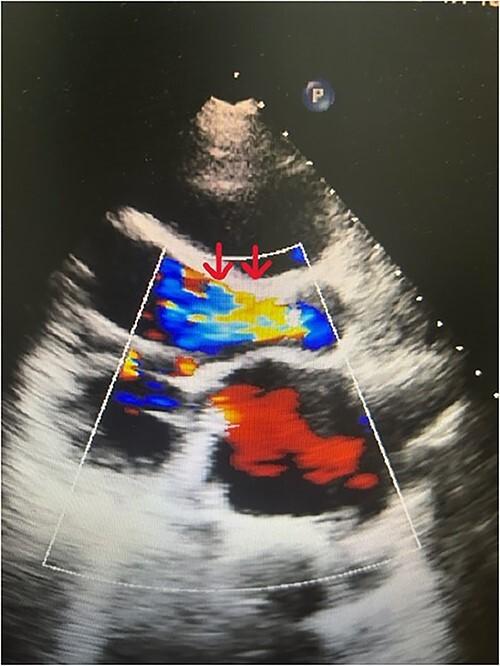

De novo aortic regurgitation (AR) presents a great challenge following left ventricular assist device (LVAD) implantation and requires valve replacement in some cases. Patients with LVAD are frequently those who underwent multiple previous sternotomies or suffer from multiple comorbidities. Thus, they are at high surgical risk for further sternotomy. Transcatheter aortic valve implantation (TAVI) previously approved for treatment of severe aortic stenosis is also used for this category of patients. Here, we report the case of a young female patient supported with heart mate II LVAD who presented with severe de novo AR. The patient was successfully treated with TAVI using Myval trancatheter heart valve (THV) in our center. To our knowledge, our patient is the first to be treated with such type of valve using TAVI procedure in LVAD supported patients.

植入左心室辅助装置(LVAD)后,新发主动脉瓣反流(AR)带来了巨大挑战,在某些情况下需要进行瓣膜置换。LVAD患者通常是那些之前接受过多次胸骨切开术或患有多种合并症的人。因此,他们接受进一步胸骨切开术的手术风险很高。先前被批准用于治疗严重主动脉瓣狭窄的经导管主动脉瓣植入术(TAVI)也用于这类患者。在此,我们报告一例接受HeartMate II LVAD支持的年轻女性患者,该患者出现严重新发AR。在我们中心,该患者使用Myval经导管心脏瓣膜(THV)通过TAVI成功治疗。据我们所知,我们的患者是首例在LVAD支持的患者中使用此类瓣膜通过TAVI手术进行治疗的。